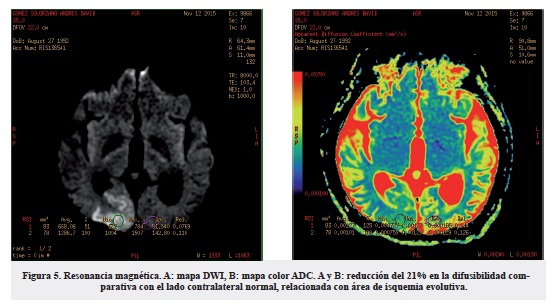

En el mapa anisotrópico del paciente estudiado, encontramos disminución anisotrópica de predominio biparietales inferiores y bioccipitales relacionados con el edema citotóxico. Al igual que reducción significativa en las fibras de asociación cortas, fibras "u" subcorticales bifrontales y con mayor compromiso biparietal y bioccipital. Se encontró además disminución significativa en el volumen y en la direccionalidad de los tractos de ambos fascículos longitudinales superiores especialmente en sus porciones posteriores. Reducción en la densidad de los tractos fronto-occipitales (figuras 4 y 5).

La anisotropía fraccional se usa para realizar una reconstrucción tridimensional de las fibras de los tractos que atraviesan la sustancia blanca, siendo más sensible que el ADC en la detección de áreas anormales cerebrales, específicamente zonas con edema extracelular que involucra los tractos de la sustancia blanca. En algunos casos el edema extracelular no es suficientemente grande como para deformar las fibras13.